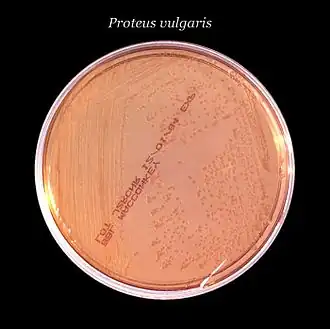

Cette deuxième forme dispose d'une propriété remarquable appelée « essaimage » (en anglais swarming)[5],[6],[7]. Il s'agit d'un type particulier de mobilité, cyclique et coordonnée, qui donne aux colonies un aspect typique en « œil de bœuf » avec des cercles concentriques qui correspondent aux vagues de migration successives à partir du point d'inoculation. L'essaimage n'est pas spécifique aux Proteus, il a également été décrit chez plusieurs autres genres bactériens tels que Aeromonas[8], Bacillus[9], Escherichia[10],[11], Pseudomonas[12],[13], Salmonella[10], Serratia[14],[15], Vibrio[16] ou encore Yersinia[17].

Les Proteus sont des bactéries sans exigence nutritionnelle particulière ce qui signifie qu'elles peuvent croître sur la plupart des milieux de base, sans nécessiter ni facteurs de croissance ni conditions de culture spécifiques. En pratique on peut les cultiver sur les géloses non sélectives (GNO, GTS etc.) ou sur les géloses « entériques » utilisées pour l'isolement des BGN (MacConkey, EMB etc). Pour inhiber ou du moins limiter le phénomène d'essaimage, qui peut gêner l'isolement des colonies, il est recommandé de modifier la composition des milieux de culture en augmentant la concentration d'agar jusqu'à 2% (m/v) et ajoutant 5 mL de glycérol par litre de milieu[3].